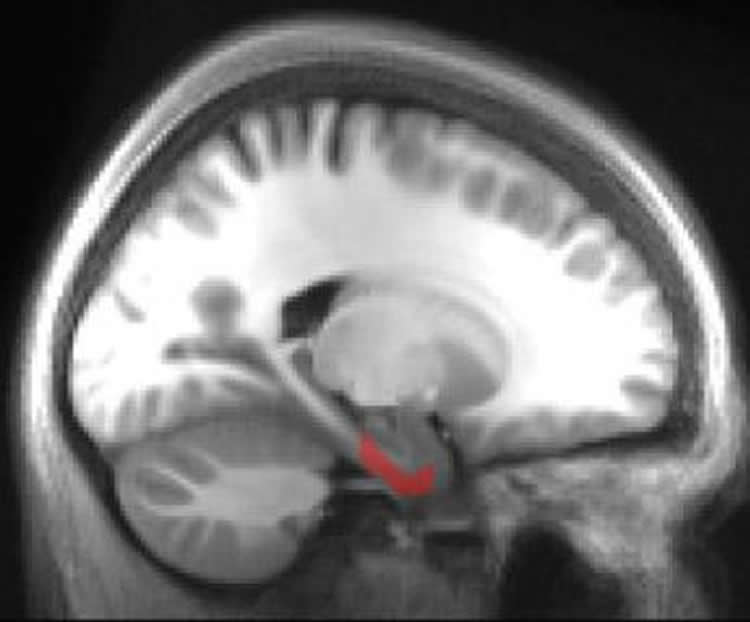

The study, published in Current Biology, used fMRI scans to detect brain activity consistent with grid cell activity in the entorhinal cortex, an important ‘hub’ for navigation and memory.

The entorhinal cortex is one of the first areas affected by Alzheimer’s disease, so the latest research could help to explain why people with Alzheimer’s can have problems imagining as well as remembering things.

Image Source: The image is credited to Professor Neil Burgess, UCL.